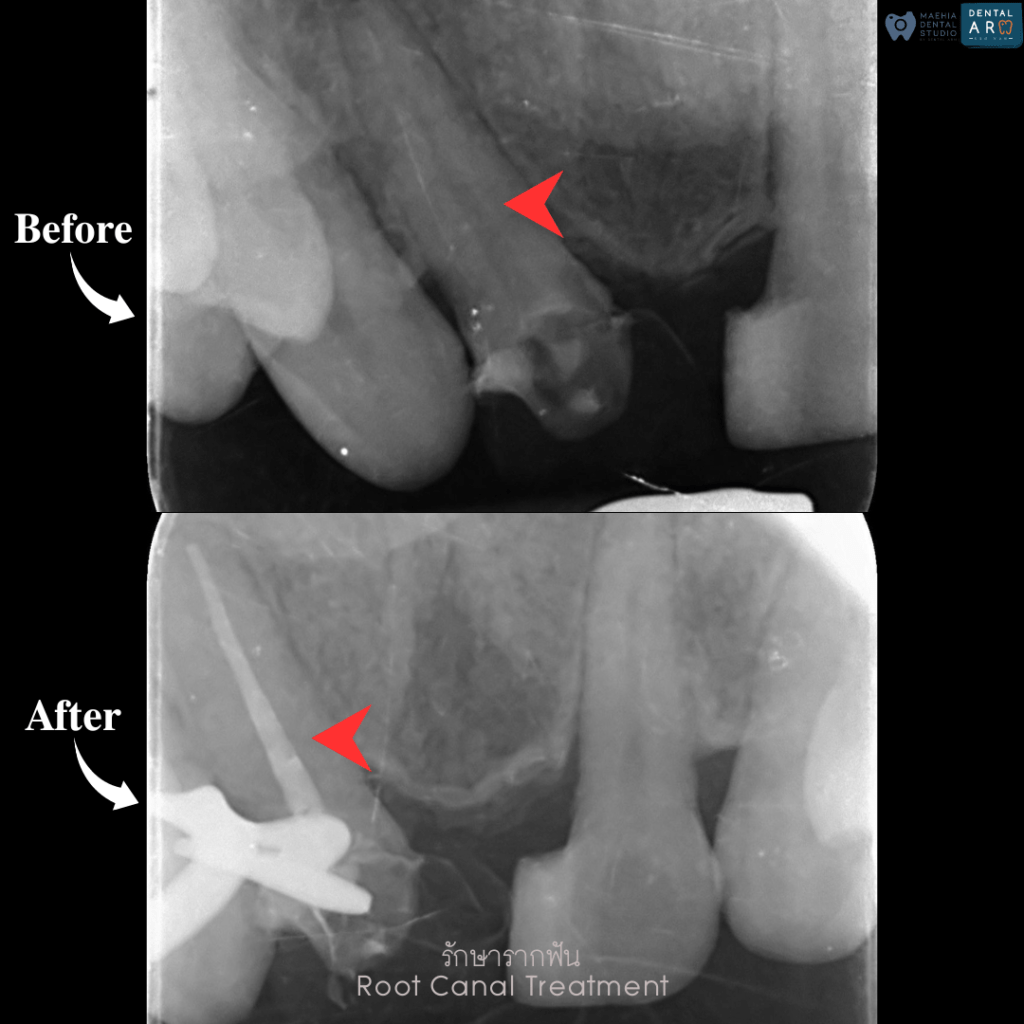

รักษารากฟัน

คือ การรักษาฟันที่เกิดการอักเสบและติดเชื้อภายในโพรงประสาทฟัน และเนื้อเยื่อรอบปลายรากฟัน อันมีสาเหตุมาการอักเสบและติดเชื้อภายในรากฟัน โดยทันตแพทย์จะทำการทำความสะอาดและใส่ยาในคลองรากฟัน และทำการอุดรากฟันเป็นขั้นตอนสุดท้าย การรักษารากฟันจะช่วยเก็บรักษาฟันให้สามารถคงอยู่ในช่องปากต่อได้ โดยไม่ต้องถอนฟันและไม่ต้องใส่ฟันทดแทน